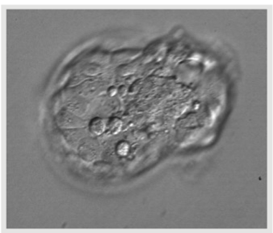

Người vợ chuẩn bị nội mạc tử cung bằng phác đồ hormone thay thế sau khi điều trị điều hoà giảm bằng phác đồ GnRH agonist. Phôi nang có chất lượng tốt nhất (4AA theo tiêu chuẩn hình thái của Gardner) được rã đông, không áp dụng hỗ trợ phôi thoát màng. Sau 2 giờ rã đông, phôi nang bắt đầu thoát màng (hình 1). SET được thực hiện dưới hướng dẫn của siêu âm ngả bụng.

Hình 1: Phôi nang thoát màng trước chuyển phôi